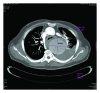

CT Diagnosis of a Thoracic Aort Aneurysm with Type B Aortic Dissection Clinically Misdiagnosed as Acute Pulmonary Embolism

A 54-year-old man was admitted to the emergency department, presenting with an acute onset of chest pain and severe respiratory distress symptoms. He was medicated with intravenous analgesia and antihypertensive drugs. The patient was subjected to a chest X-ray which revealed a prominent widening of the mediastinum and pleural effusion on the left side. In laboratory tests-d-dimer level was highly elevated. The patient was clinically interpreted as having an acute pulmonary embolism and referred to the radiology clinic to perform a computed tomography (CT) examination. Contrast-enhanced CT demonstrated that there was no abnormality related to the pulmonary vasculature, but a huge thoracic aorta aneurysm measuring 11 × 8.1 × 7.7 cm in diameter was detected. Accompanying the aneurysm, an intimal flap was also present in the proximal descending thoracic aorta, distal to the origin of the left subclavian artery and extending into the bifurcation level. The patient was therefore diagnosed as having a type B aortic dissection as well. Once these serious conditions were detected, he was immediately transferred to a cardiovascular thoracic surgery hospital for endovascular repairment operation.